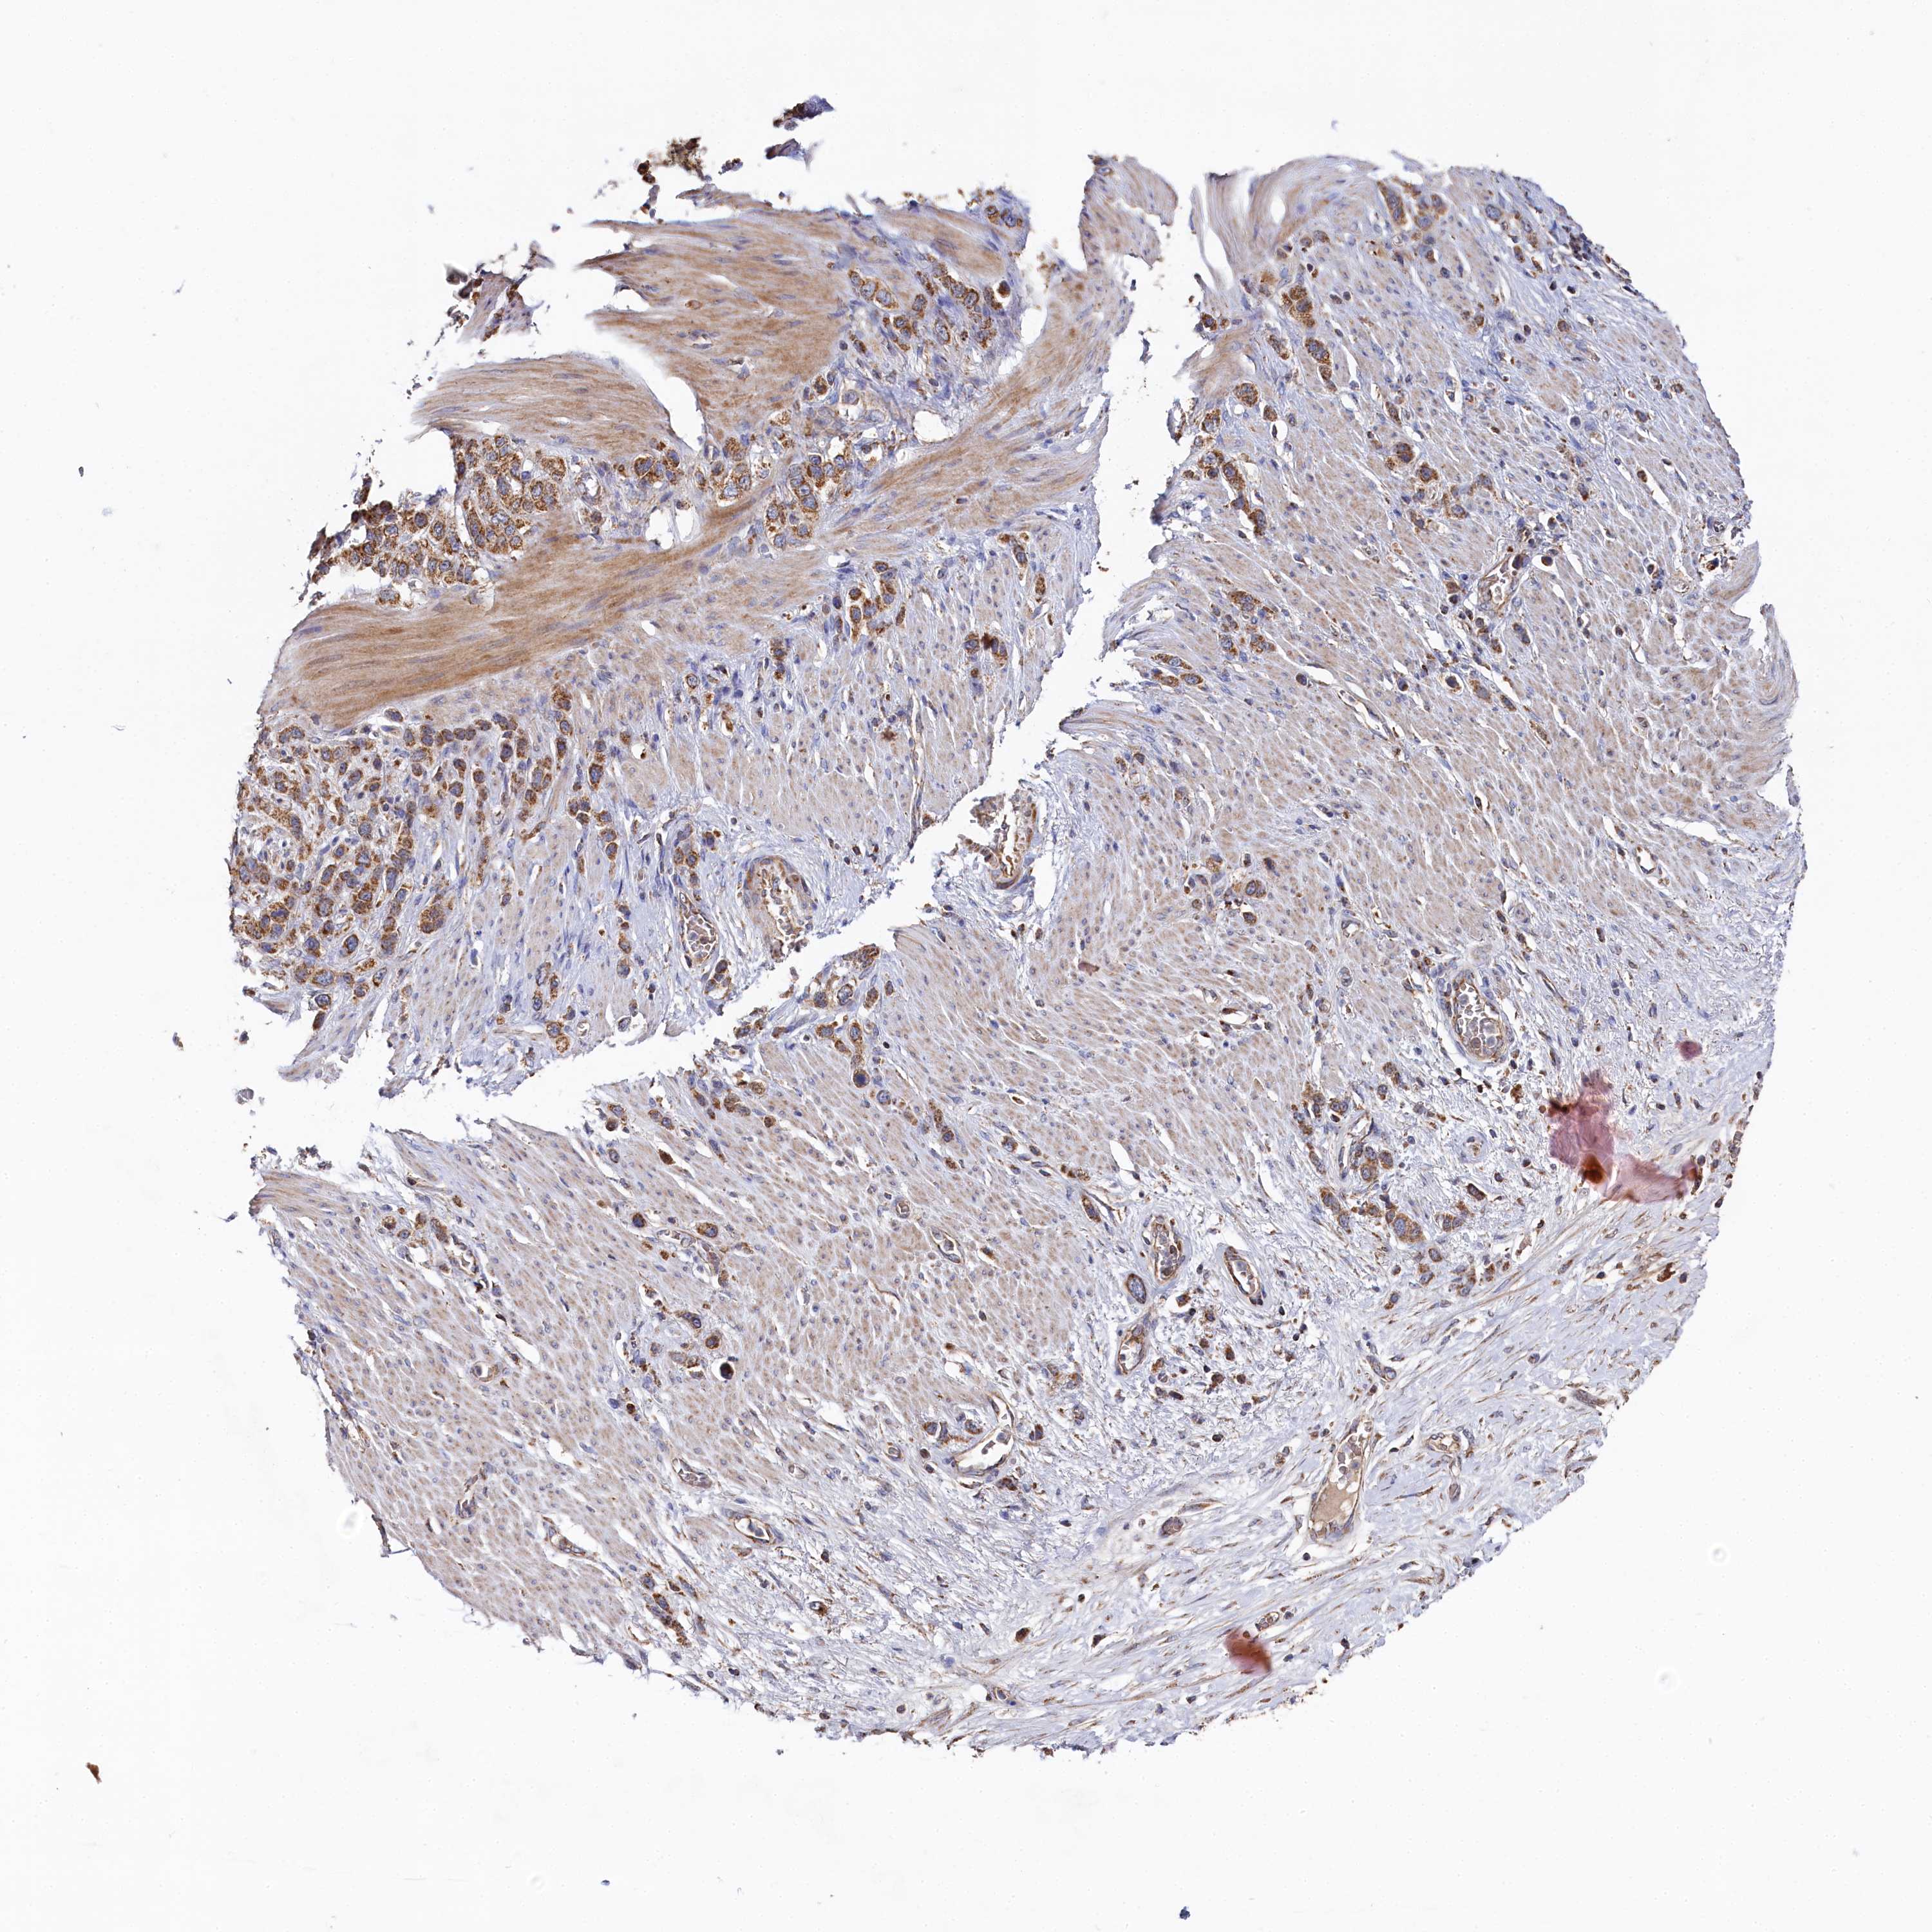

STOMACH CANCER - Protein expressioni

A mouse-over function shows sample information and annotation data. Click on an image to view it in a full screen mode. Samples can be filtered based on level of antibody staining by selecting one or several of the following categories: high, medium, low and not detected. The assay and annotation is described here.

Note that samples used for immunohistochemistry by the Human Protein Atlas do not correspond to samples in the TCGA dataset.

Antibody stainingi

Antibody staining in the annotated cell types in the current human tissue is reported as not detected, low, medium, or high, based on conventional immunohistochemistry profiling in selected tissues. This score is based on the combination of the staining intensity and fraction of stained cells.

Each image is clickable and will lead to virtual microscopy that enables deeper exploration of all samples and also displays staining intensity scores, fraction scores and subcellular localization as well as patient and tissue information for each sample.

Antibody HPA039965

Staining

High

Medium

Low

Not detected

Intensity

Strong

Moderate

Weak

Negative

Quantity

>75%

75%-25%

<25%

None

Location

Nuclear

Cytoplasmic/membranous

Cytoplasmic/membranous,nuclear

Adenocarcinoma, NOS

Adenocarcinoma, High grade